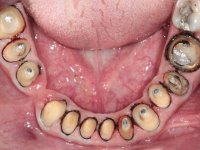

Paciente do sexo masculino, com 42 anos de idade, não fumador. Apresentava uma reabilitação metalo-cerâmica feita há mais de 10 anos com exposições radiculares e infiltrações. No maxilar superior apresentava uma coroa no 1.1,uma ponte de dois elementos no 2.1 e 2.2.e uma ponte de 4 elementos nos dentes 2.4,2.5,2.6 e 2.7 com o 2.6 como pôntico. Os dentes 1.6/1.5/1.4/1.3/1.2/1.1/2.1/2.2/2.3/2.4/2.5 e 2.7 apresentam tratamento endodôntico radical com o 2.4/2.5 e 2.7 a necessitarem de ser refeitos. No maxilar inferior apresentava uma ponte metalo-cerâmica de 4 elementos nos 4 incisivos e uma ponte de 3 elementos (3.3 e 3.4) com um dente supranumerário como pôntico. Os dentes 4.6/4.5 e 4.2 apresentavam tratamento endodôntico com o 4.2 a necessitar de ser refeito. Os dentes 4.3 e 4.4 apresentavam extensas cáries linguais com algum comprometimento mesial. As peças protéticas apresentavam-se infiltradas com exposição radicular associada. Apresentava uma D.V.O. diminuída e uma mordida cruzada lado direito. O paciente tinha uma satisfatória saúde periodontal e uma boa higiene oral.

Foi proposto ao paciente fazer uma reabilitação total com infraestruturas em zircónia revestidas a cerâmica. No maxilar superior, seriam realizadas 6 coroas (1.3/1.2/1.1/2.1/2.2/2.3), uma ponte de 3 elementos (1.4/1.5/1.6) e uma ponte de 4 elementos (2.4/2.5/2.6 e 2.7). No maxilar inferior, foram propostas 7 coroas (4.3/4.2/4.1/3.1/3.2/3.5 /3.6) e duas pontes (4.4//4.5/4.6) e (3.3/3.4#/3.4).O objetivo seria subir a D.V.O., descruzar a mordida do lado direito, eliminar as infiltrações e as exposições radiculares e reabilitar o paciente com estruturas protéticas com aspeto mais natural.